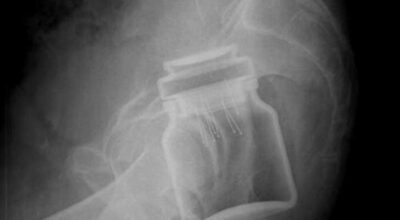

Esta recopilación de imágenes recoge alguna de las situaciones más estrambóticas que se han podido dar en una sala de rayos X. Todas ellas tienen algo en común: Son objetos extraños para el cuerpo humano que, de alguna manera han encontrado una vía de entrada, pero se han perdido a la hora de encontrar la de salida.

Muñecas de juguete descabezadas, botellas, armas, frascos, botes de plástico, teléfonos y hasta una cinta de casete pueden encontrarse en esa suerte de “punto limpio” al que ha quedado reducido el interior de los afectados.